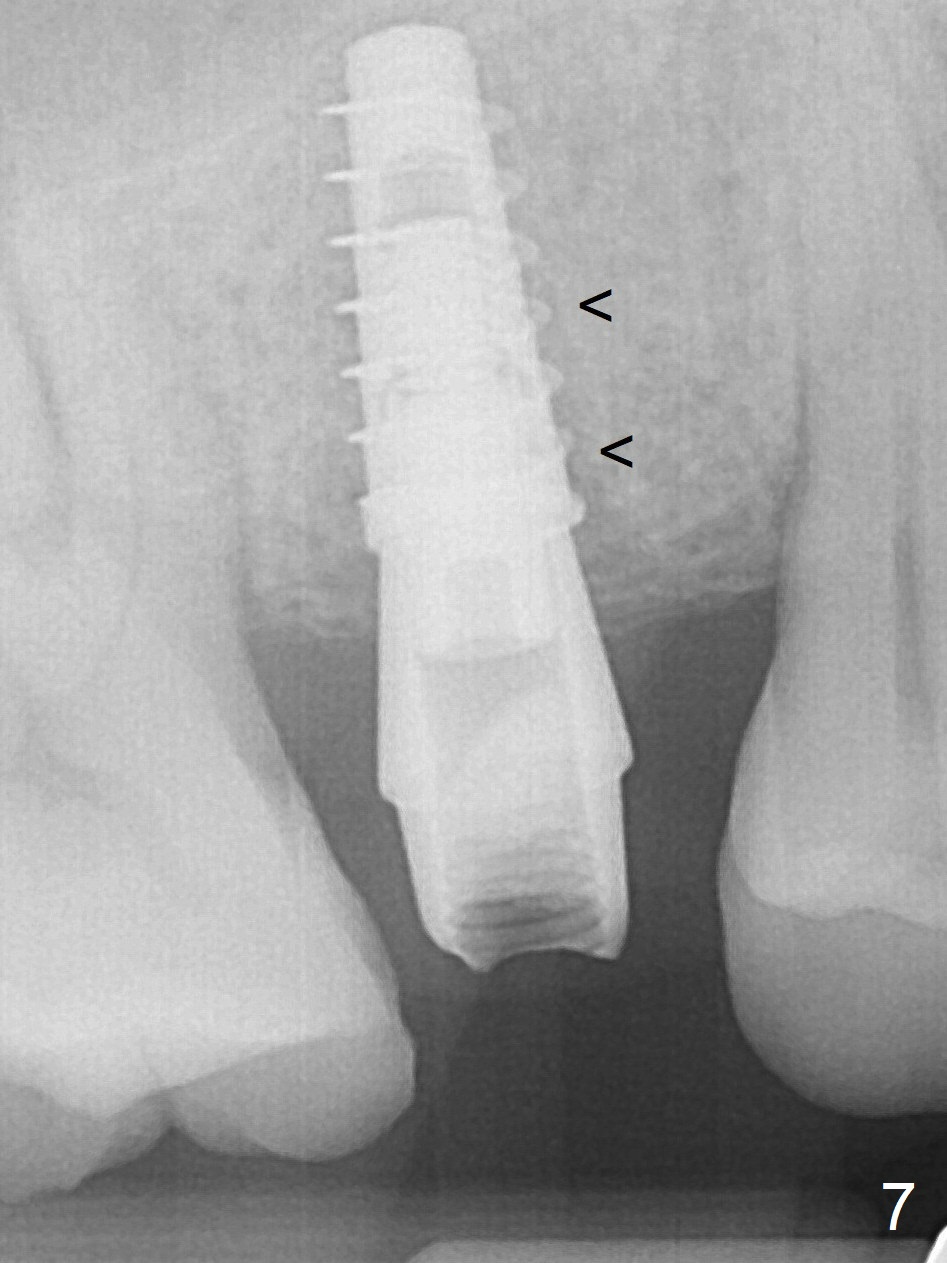

After extraction without drilling, a 4x11 mm dummy implant is placed as a tap drill with satisfactory stability (Fig.5).  To get subcrestal placement, a shorter (4x9 mm) implant is inserted with insertion torque of >35 Ncm (Fig.6).  In retrospect, a larger implant (4.5 mm) would be better in term of primary stability.  After allograft placement into the buccal and lingual gaps, a 4.5x4(4) mm abutment is placed for an immediate provisional.  The sinus floor is penetrated by the implants without bone graft for sinus lift.  There is a peri-implant gap 7 months postop (Fig.7<) .  When the loose abutment is being retightened, the patient feels pain, although the gingiva appears healthy (Fig.8).  A larger implant should have been used; the abutment should have been removed.